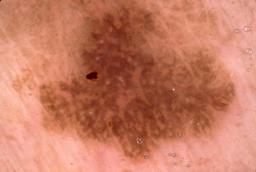

{

"age_approx": 75,

"anatom_site_general": "head/neck",

"concomitant_biopsy": true,

"dermoscopic_type": "contact non-polarized",

"diagnosis_1": "Malignant",

"diagnosis_2": "Malignant melanocytic proliferations (Melanoma)",

"diagnosis_3": "Melanoma, NOS",

"diagnosis_confirm_type": "histopathology",

"image_type": "dermoscopic",

"lesion_id": "IL_4116158",

"melanocytic": true,

"patient_id": "IP_4497472",

"sex": "male"

}